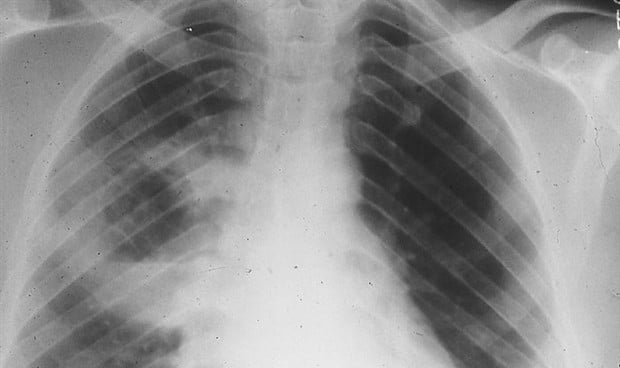

La fibrosis pulmonar idiopática (FPI) es un tipo de enfermedad pulmonar que produce cicatrices en los pulmones, que empeora con el tiempo, lo que se vuelve difícil para las personas con la enfermedad simplemente respirar profundamente para obtener el oxígeno que necesitan.

Sin embargo, no está claro cuál es la causa de esta afección, y si bien hay dos tratamientos que pueden ayudar a disminuir la velocidad a la que progresa la FPI, actualmente no existe un tratamiento que pueda detener o revertir la cicatrización del pulmón.